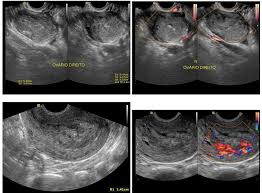

Slideshow endométrio heterogêneo o que significa

Endométrio heterogêneo